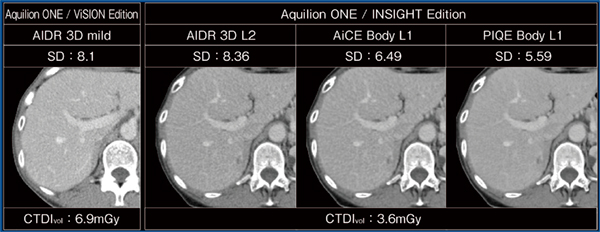

3.新型検出器+新型X線管

新型検出器の最大の特長として,電気ノイズが従来比で約40%低減されたことが挙げられる。図1は,同社の従来CTとAquilion ONE / INSIGHT Editionの画像比較で,共に「Adaptive Iterative Dose Reduction 3D(AIDR 3D)」使用,5mmSD:11で肝実質を撮影し,それぞれのSDを計測した。AIDR 3Dを用いた場合のSD値は両装置とも同等であるが,Aquilion ONE / INSIGHT Editionの画像にDeep Learning Reconstruction(DLR)を適用することでSD値が向上し,特に「Precise IQ Engine(PIQE)」では5.59にまで向上していた。また,CTDIvolは従来CTの6.9mGyに対し,Aquilion ONE / INSIGHT Editionでは3.6mGyと,大幅な被ばく低減が可能であった。

図1 従来CTとAquilion ONE / INSIGHT Editionの画像比較

AiCE:Advanced intelligent Clear-IQ Engine